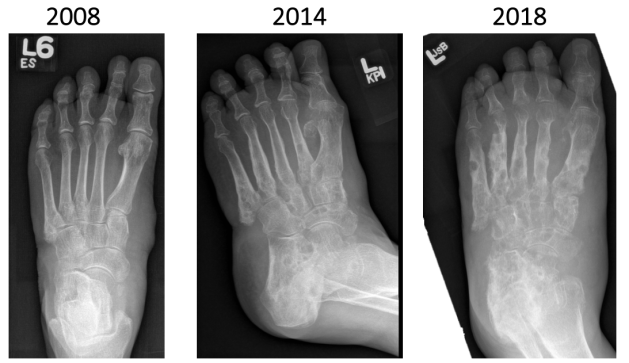

X-rays…

- 2008 – saw ID as still bothering her